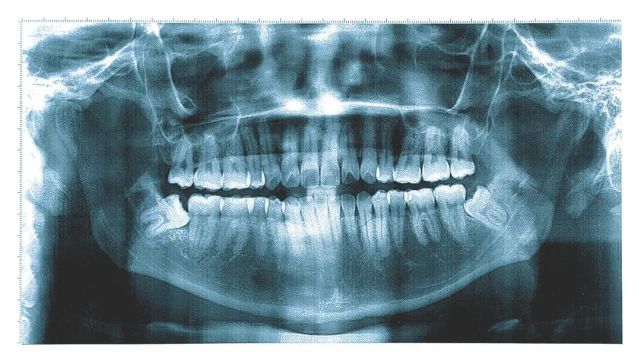

吃饱喝足拍完口腔全景片后,局长人生第一次看到自己的牙齿结构:

图片

医生:你很幸运只长了三颗阻生齿,可以少拔一颗局长:可以同时拔掉吗?医生:不建议同时拔,最好是拔了一边,等1-2周拔牙创口愈合了,再回来拔另一边的。躺下吧,先打麻药。